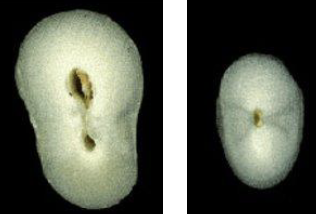

What is the anatomical variation in this lateral incisor?

Dens invaginatus